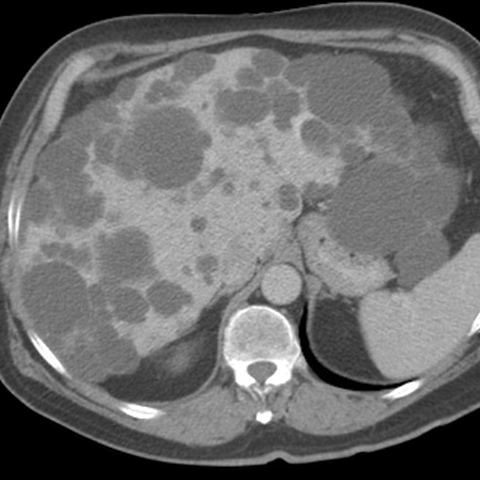

46 year-old male presents with increasing abdominal girth. [1 of 2]